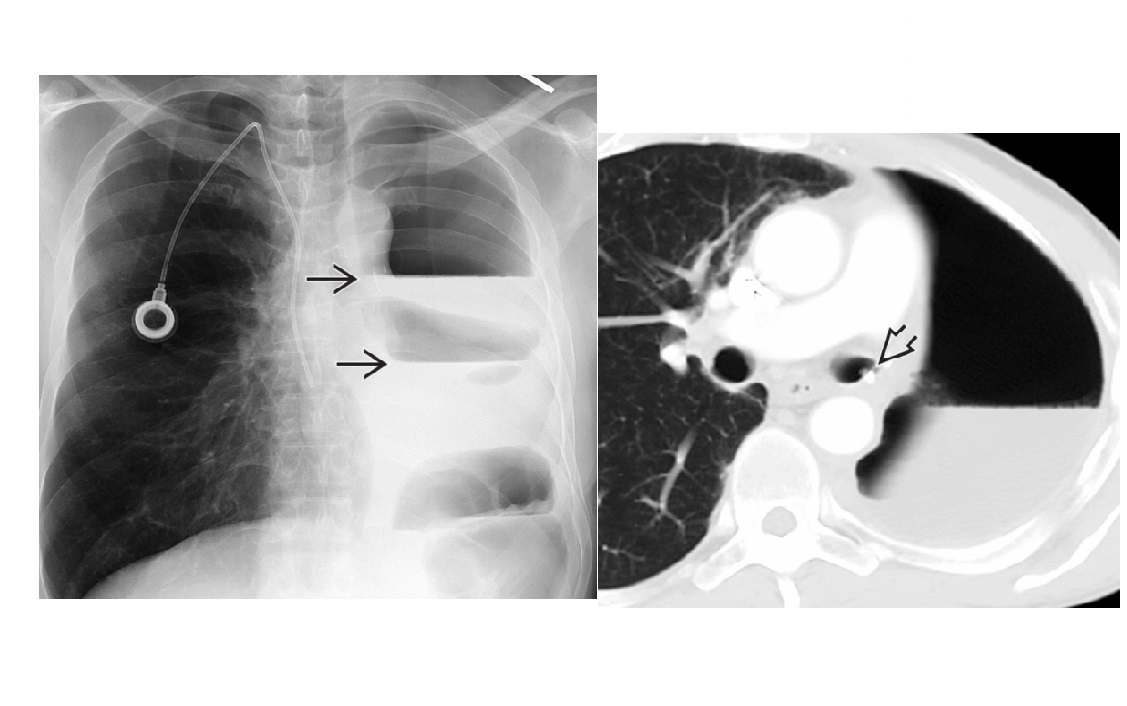

Bronchopleural fistula

Post pneumonectomy

contralateral tracheal shift

Reduction on height of fluid on sequential films.

Can confirm on Xenon gas nuclear med

Normal appearances -

air fluid level at day4/5, by 14 days 100% fluid filled

ipsilateral tracheal shift

Diaphragm elevation